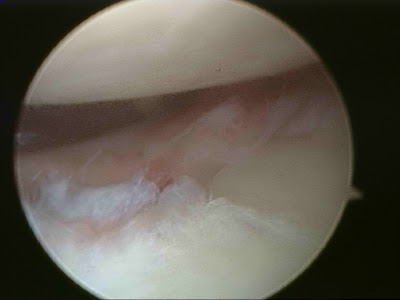

Picture above showing Labral detachment